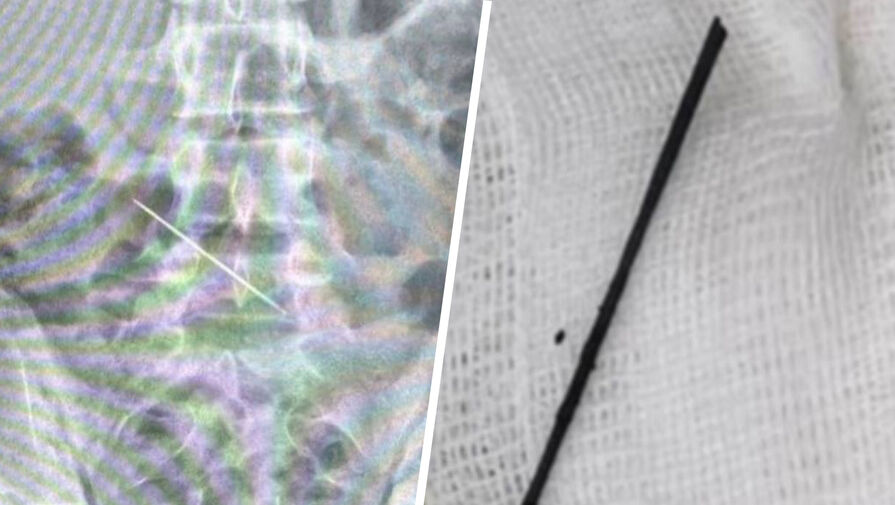

Школьник поступил в больницу с подозрением на аппендицит, однако первоначальный диагноз не подтвердился. Обследование показало, что в подреберье пациента в подреберье зафиксирован инородный предмет — пятисантиметровая швейная игла. Она застряла в поперечной ободочной кишке и проткнула ее.

«Игла выступала ушком в просвет брюшной полости — в брызжеечной части кишки, где более толстая стенка. По этой причине, а также из-за малых размеров и раннего обнаружения отверстие не нарушило герметичность кишки, поэтому перфорация зажила самостоятельно без ушивания», — рассказал детский хирург Максим Сергеенко.